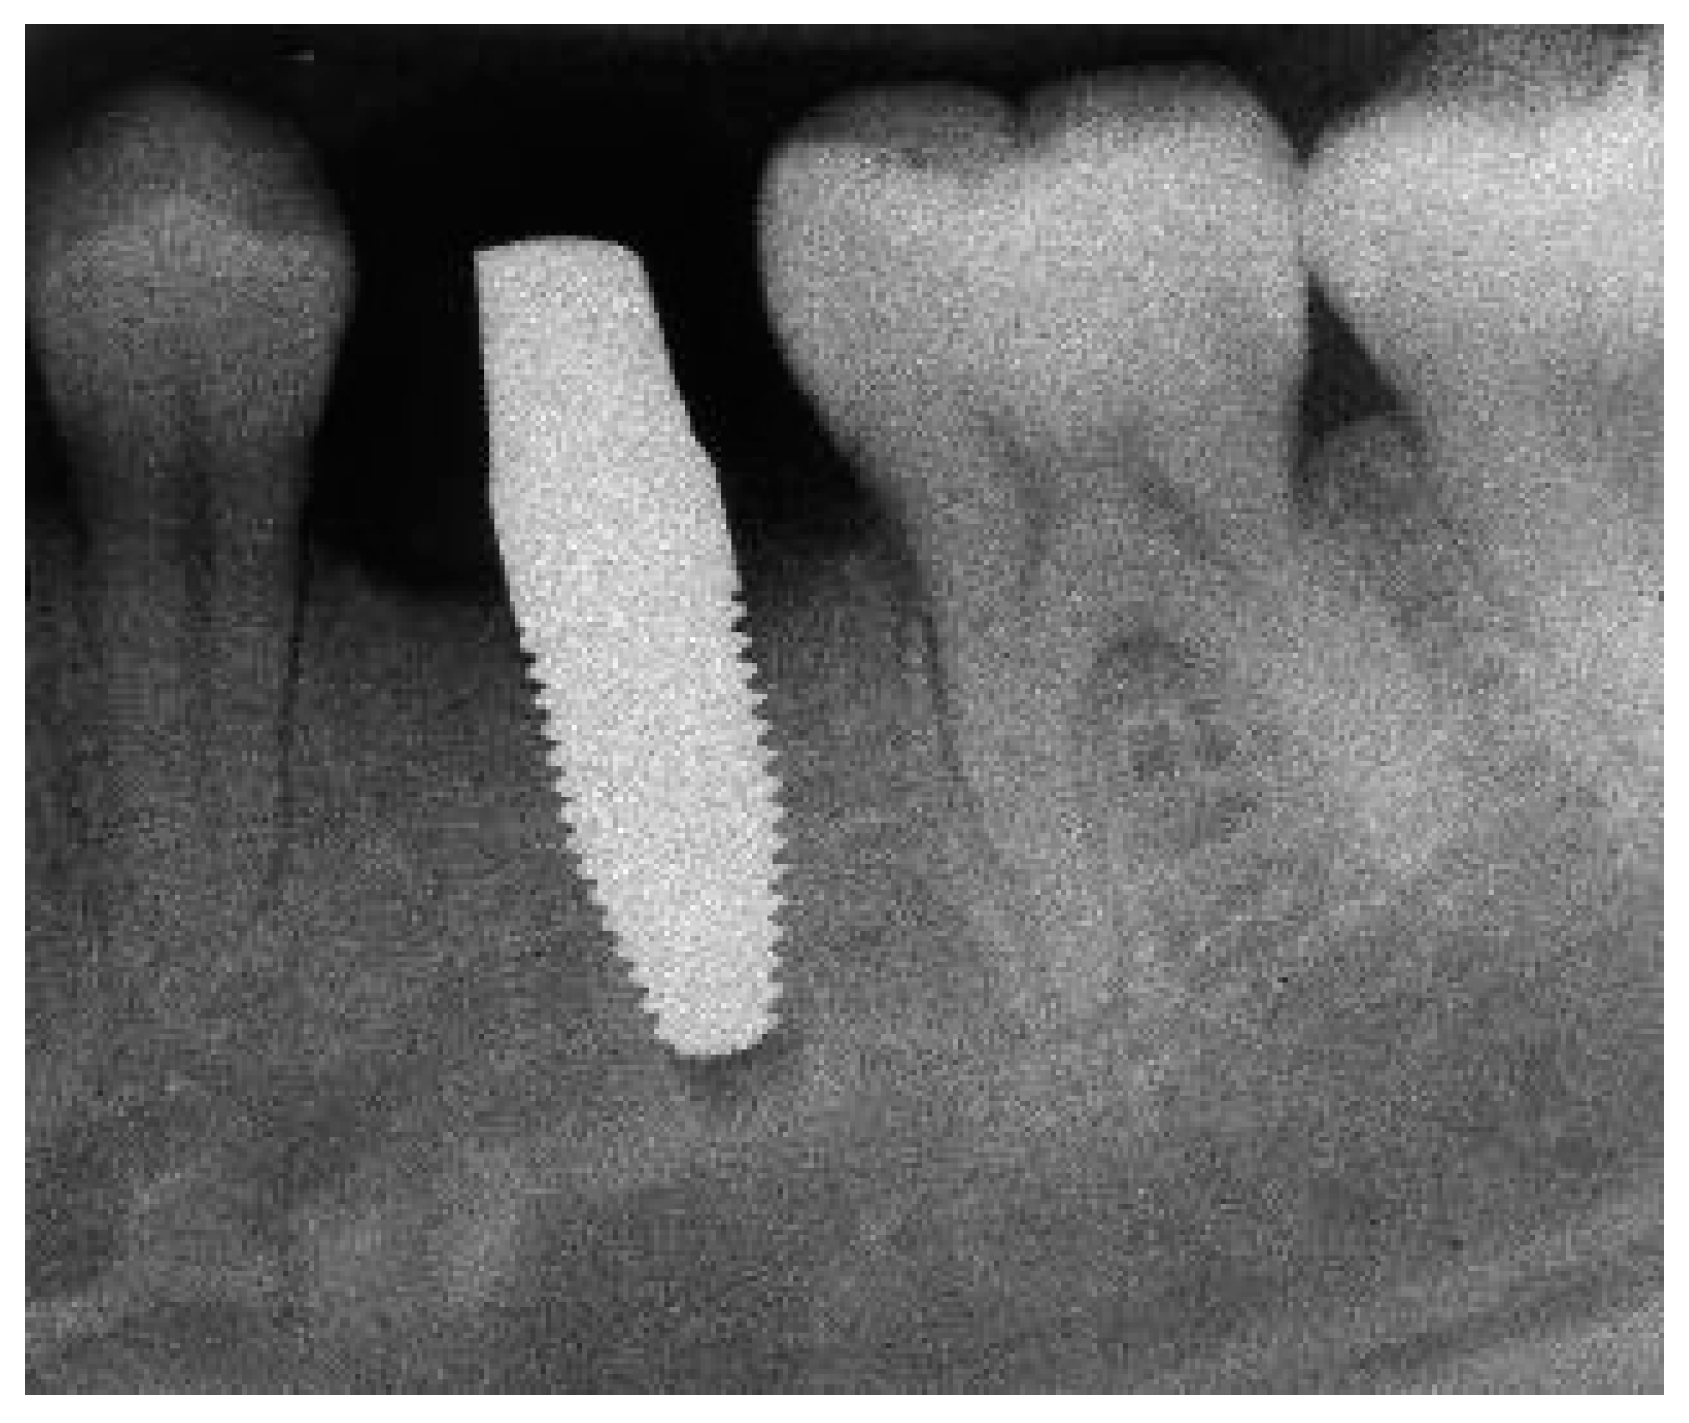

Appendix A. Exemplary Photographs and Radiographs from a Patient at Different Examination Time Points and a Positive Outcome

Appendix B. Exemplary Photographs and Radiographs from a Patient at Different Examination Time Points and a More Negative Outcome